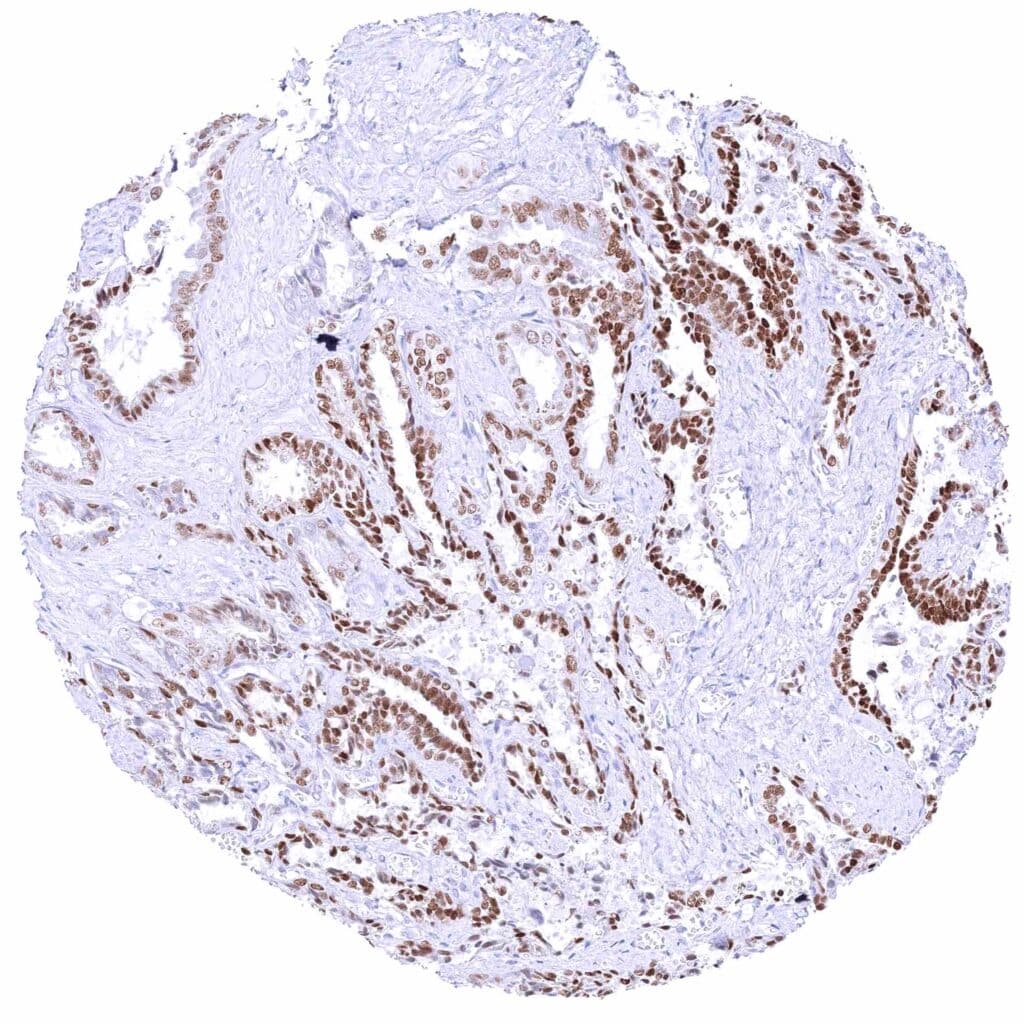

Breast – Moderate to strong GATA3 staining of luminal cells while myoepithelial cells remain GATA3 negative.